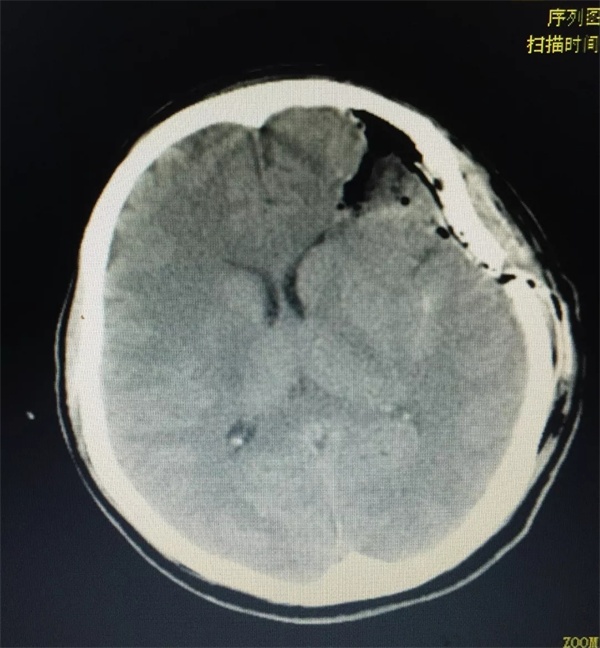

2018年12月1日上午11时30分,家住红谷滩新区的18岁美少女佳佳在坐车回家途中,突然出现剧烈头痛,继而陷入昏迷,旁边的朋友紧急呼叫120把她送入捕鱼游戏 。 入院查体: 体温:36.5°,脉搏80次/分,呼吸20次/分,血压:121/69mmHg。双肺呼吸音清晰,未闻及干湿性罗音; 神经系统检查:神志嗜睡,呼唤睁眼,语言清晰,对答基本切题,双侧瞳孔等大等圆,直径3.0mm,光反应存在,眼球活动度好,鼻唇沟不变浅,伸舌居中,咽反射存在,转颈,耸肩好。颈软,克氏征阴性。四肢肌力肌张力正常,双侧感觉检查无异常,双侧腱反射对称,双侧病理征未引出,双侧指鼻试验、跟膝胫试验完成可。 急诊头颅CT:左侧额叶出血,左侧急性硬脑膜下血肿,左侧外侧裂池积血。

手术目前是脑血管畸形最主要也是最有效的治疗手段。由于脑动静脉畸形的血管发育异常,手术出血凶险、止血困难,对神经外科医生手术技术和多学科团队配合要求高。目前捕鱼游戏 影像科设备齐全,图像质量好,诊断水平高,对脑动静脉畸形的确诊率在95%以上,神经外科手术团队和介入团队针对脑动静脉畸形已全面开展显微手术切除和介入栓塞工作。